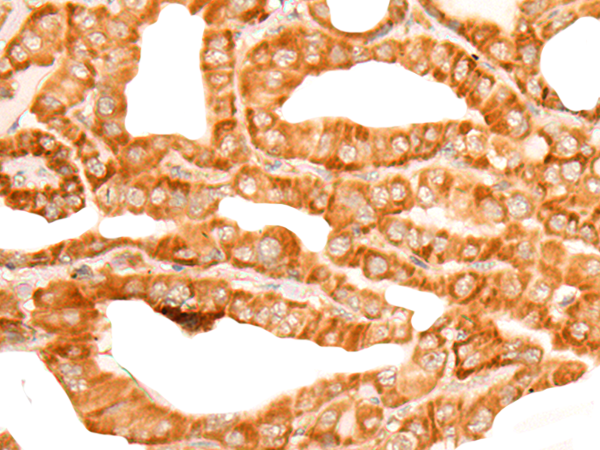

IHC positive control: |

Human liver cancer and Human thyroid cancer |